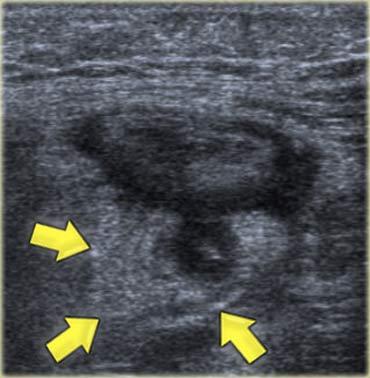

Lâm sàng nghi viêm ruột thừa. Siêu âm chỉ phát hiện một lượng nhỏ dịch cổ trướng. Chọc dò chẩn đoán (mũi tên chỉ đầu kim) cho thấy dịch máu. Ở phụ nữ, phát hiện này rất nghi ngờ thai ngoài tử cung (EUG).